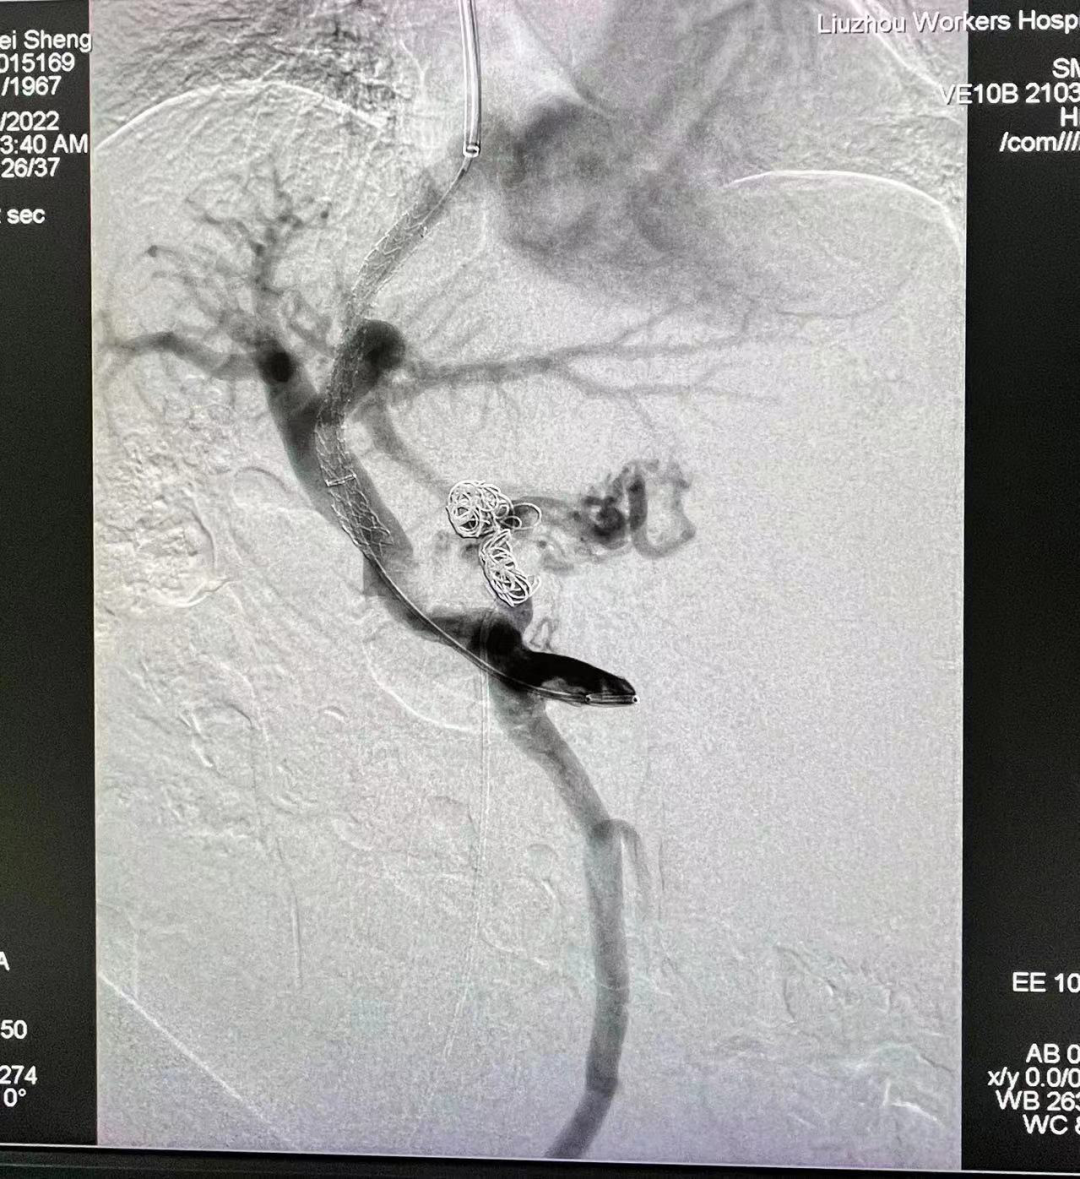

TIPS支架植入后门静脉造影:支架通畅,分流良好